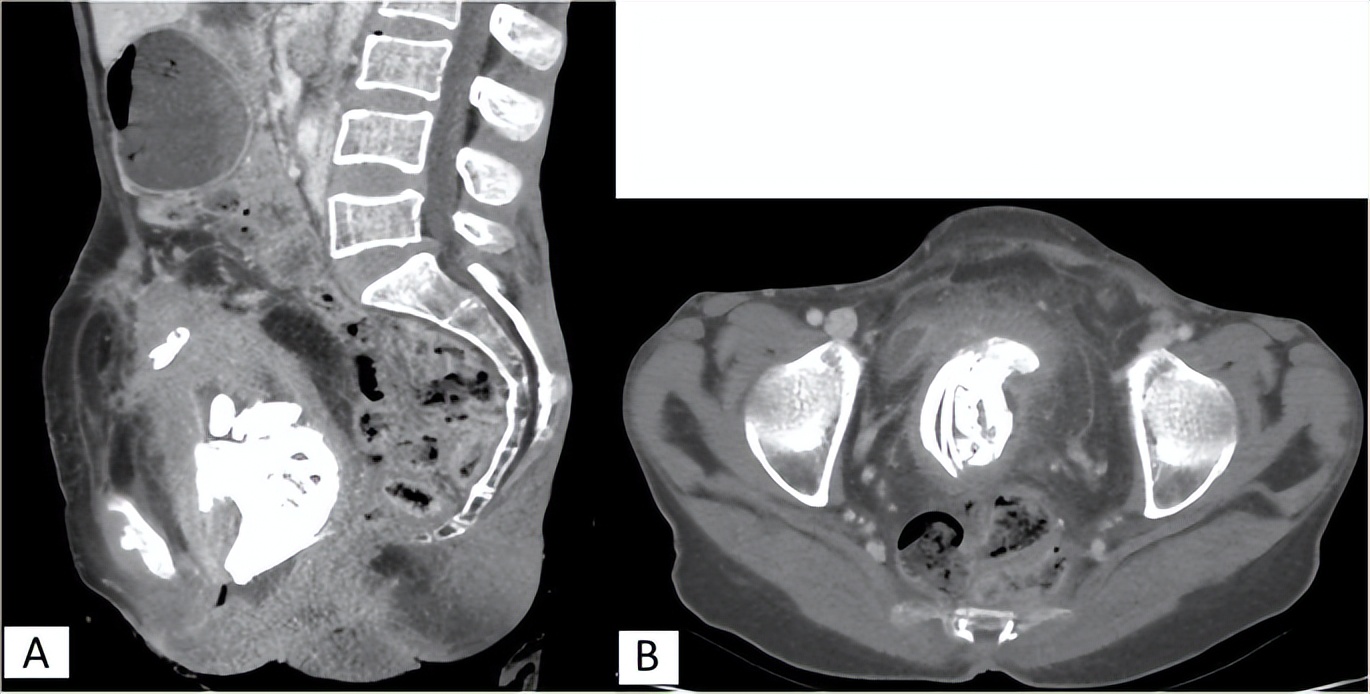

(一名埃塞俄比亚女性的石胎扫描,该石胎已在她体内20年。)

根据CT扫描的发现,她的腹中有一个长15-20厘米的石胎,能清晰看到胎儿的骨架。因为石胎体积较大,压迫了她的诸多脏器,导致了一系列健康问题。